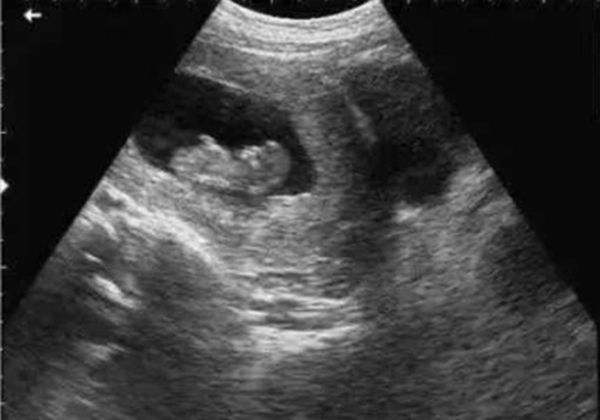

? 超聲檢查(B超/彩超):它利用超聲波的反射原理成像,就像“用聲音給身體拍照片”,沒(méi)有任何輻射。無(wú)論是孕期產(chǎn)檢(觀察胎兒發(fā)育)、腹部檢查(排查肝脾膽囊問(wèn)題),還是甲狀腺、乳腺等淺表器官檢查,超聲都是首選。而且超聲檢查靈活便捷,還能實(shí)時(shí)動(dòng)態(tài)觀察器官運(yùn)動(dòng)(比如心臟跳動(dòng)、胎兒胎動(dòng)),是臨床中應(yīng)用最廣泛的“安全檢查”。

當(dāng)然,在非緊急情況下,醫(yī)生會(huì)優(yōu)先選擇超聲或MRI。比如孕婦產(chǎn)檢,超聲是核心檢查;嬰幼兒排查腦部問(wèn)題,MRI是更安全的選擇。關(guān)鍵在于“權(quán)衡利弊”,而非“一刀切”拒絕。